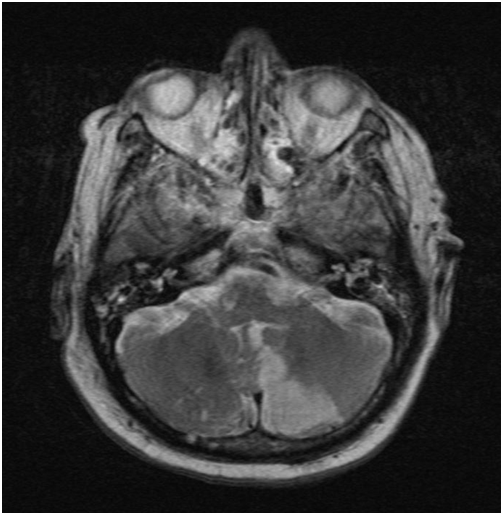

After surgery a slurred speech and a deviation of the eyes were observed. The MRI (1,5 T, T1w SE sagittal, FLAIR coronar, T2w TSE transversal, bleeding- and diffusions sensitive sequences T2w TSE sagittal TOF angiography and secondary multiplanar reconstructions) showed multiple ischemic regions in the dorsal flow area of the cerebellum on both sides, especially in the pica flow area, the left thalamus, left temporal and occipital due to multiple embolisms (Figure 3). Space occupying cerebral edema was not found.

Figure 3 Cerebral magnetic resonance imaging. The diffusion sensitive sequences (T2w TSE) show a left sided ischemia of the cerebellum following surgery.